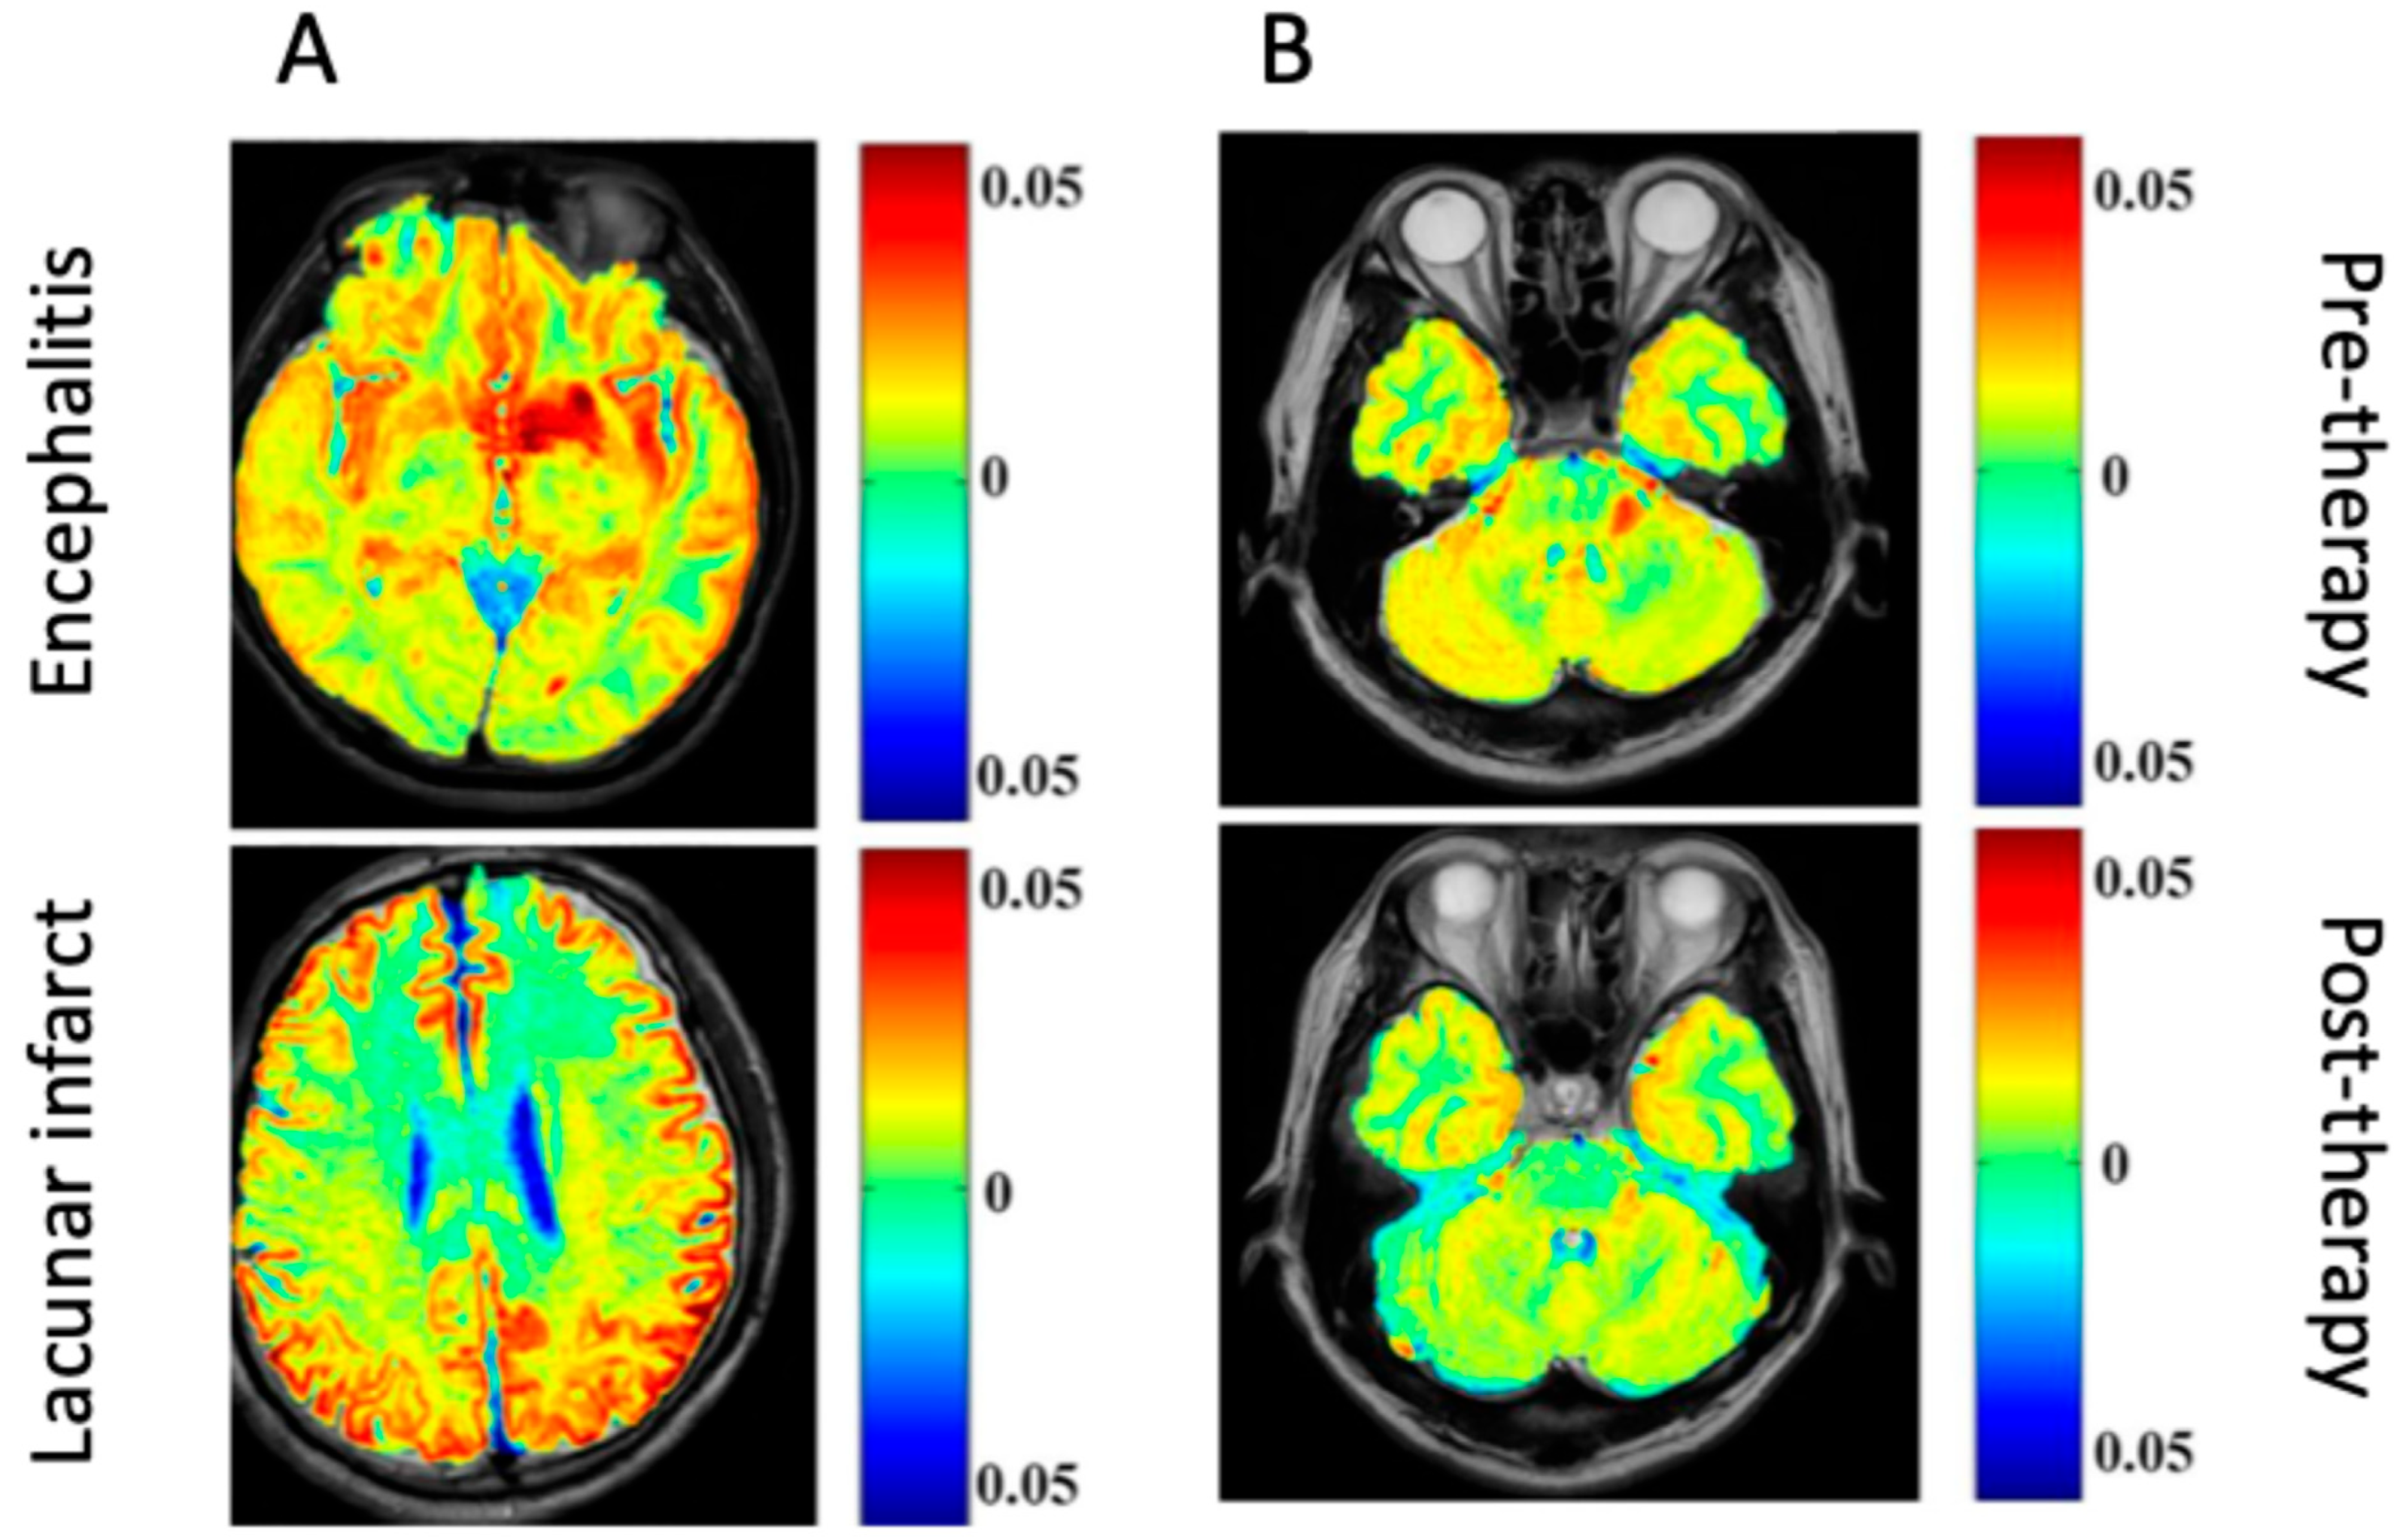

In particular, CEST has significant diagnostic potential in differentiating infective pathogenesis in the CNS from other lesions (e.g., ischemic, neoplastic). The bacCEST study [45] was able to differentiate brain abscesses and tumors, which is currently unreliable with conventional MRI techniques. Still, a statistically significant difference between the abscess and tumor signal was recorded using different B1 values (1 μT and 3 μT for brain abscess and tumor, respectively. This relationship was preserved when tested with two different tumor models in rats (specimens were injected with F98 or 9 L glioma cell lines). The gluCEST signal has also successfully distinguished between encephalitis and ischemic lesions, where glutamate concentrations are found to be decreased in lacunar infarction regions but increased in encephalitis lesions [46].

The severity of lesions in encephalitis can also be tracked over time with gluCEST during intravenous immunoglobulin therapy. The gluCEST signal in encephalitis lesion areas was significantly decreased from pre- to post-treatment in human participants, which correlated with the signal intensity changes visualized on conventional MRI imaging [46]. However, the gluCEST signal change was specific to encephalitis lesions; lacunar infarction lesions treated with the same therapy could not be adequately visualized over time with gluCEST [46].

Generally, differences in the imaging between different events in the brain could provide a wrong diagnosis. For example, the difference between encephalitis and lacunar infarction could not provide a differential picture for an accurate diagnosis. However, a clinical study demonstrated an increase in the gluCEST signal in patients with encephalitis compared to a decreased gluCEST signal in patients with lacunar infarction [46]. To validate their finding, patients with encephalitis were treated with a cocktail of immunoglobulins, which caused a decrease in the encephalitis lesions (1.34% to 5%) (Figure 2).

Figure 2.

Glutamate chemical exchange saturation transfer (gluCEST) in patients. (A) Differential images comparing encephalitis and lacunar infarct. (B) Images showing encephalitis before and after immunoglobulin therapy [46] (Images obtained from an open-access article distributed under the terms of the Creative Commons Attribution License (CC BY)).